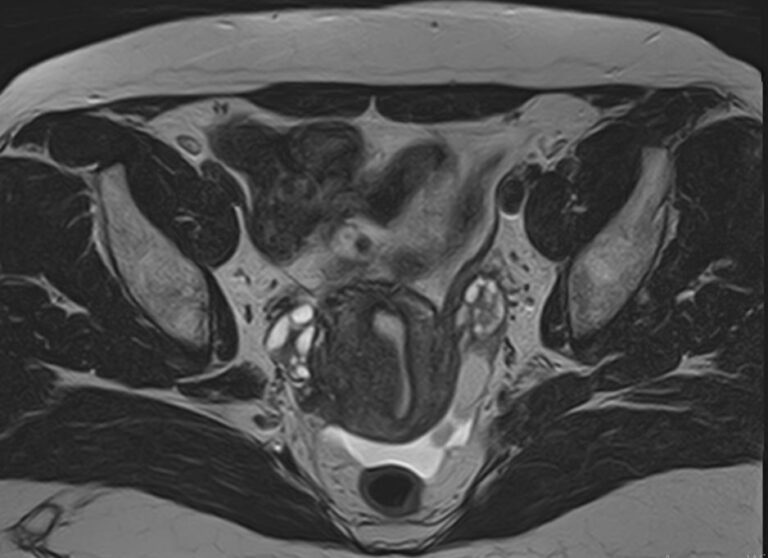

С помощью данного исследования можно получить детальное послойное изображение матки, яичников, мочевого пузыря и мочеотводящих путей, а также жировой клетчатки, окружающей органы, и лимфатических узлов.

• Сужения или обструкцию (закупорку) мочеточника, изменения уретры (мегауретер и т.д.);

• Изменения лимфатических узлов и жировой клетчатки, распространение метастазов в них;

• Поражения мочевого пузыря (эндометриоидную ткань, новообразования и др.);

• Заболевания прямой кишки (опухоли, свищи).